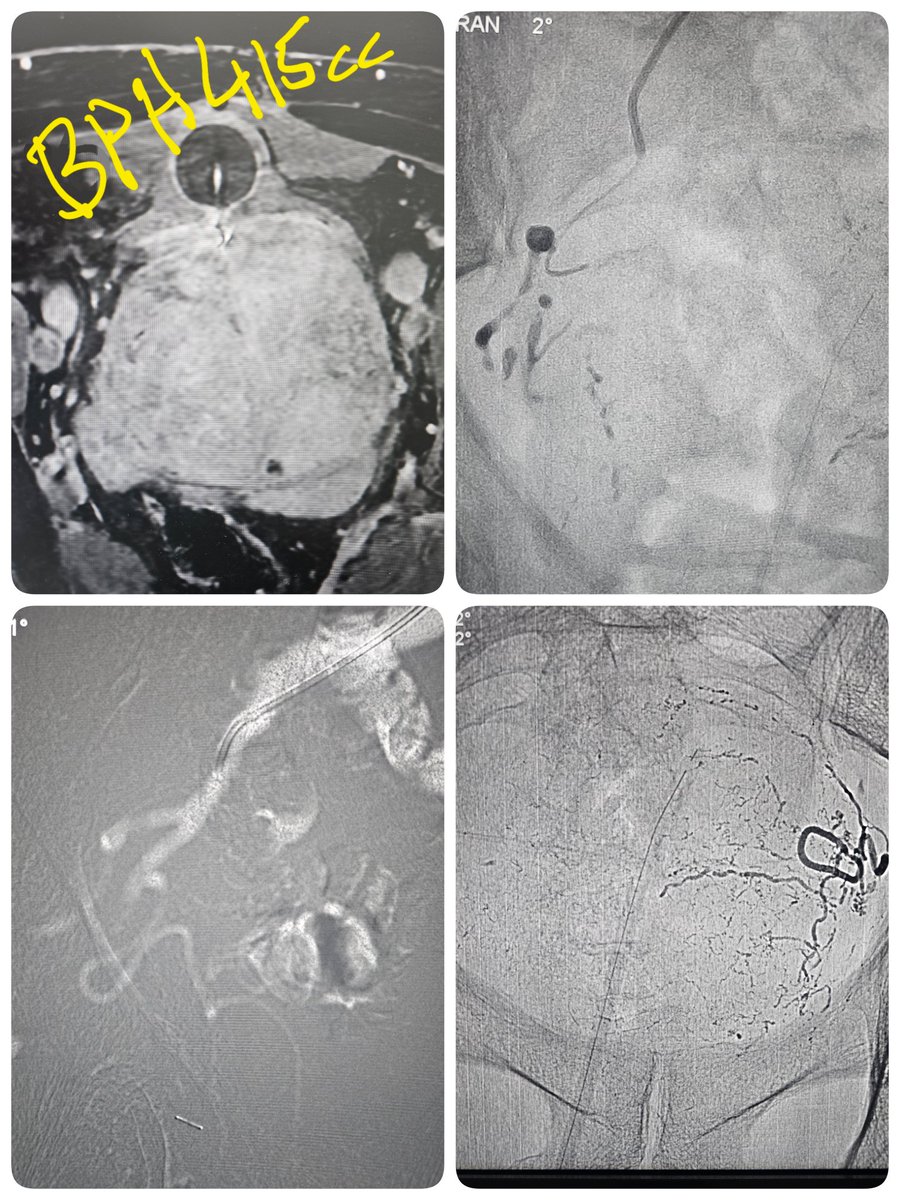

Co2 PAE Glue , only 10 cc Visipaque, BPH recurrence post laser علاج تضخم البروستاتا بإغلاقها بالصمغ بإستخدام غاز ثاني أكسيد الكربون لإرتفاع وظائف الكلى وتقليل كمية الصبغه مركز عيادات دوالي 🥼 د محمد الطواله Altwalah